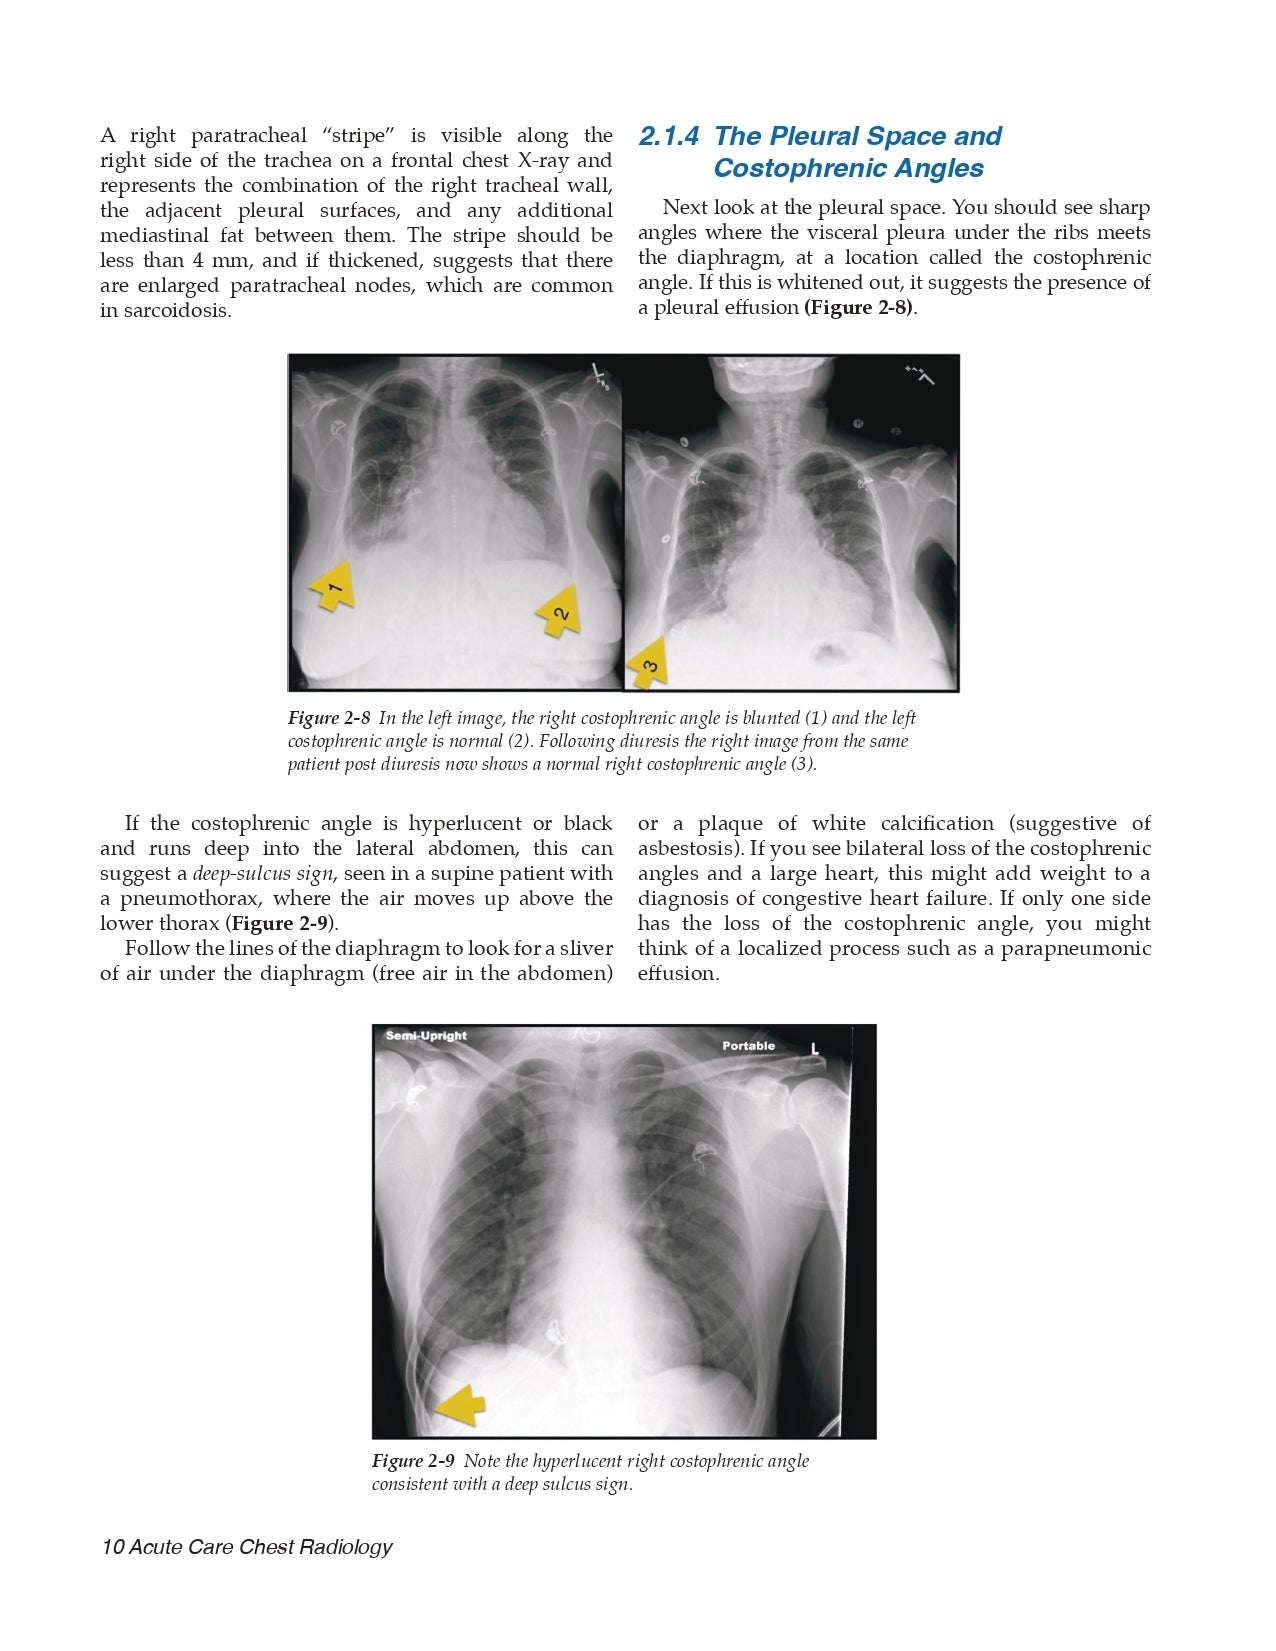

- The Pleural Space and Costophrenic Angles